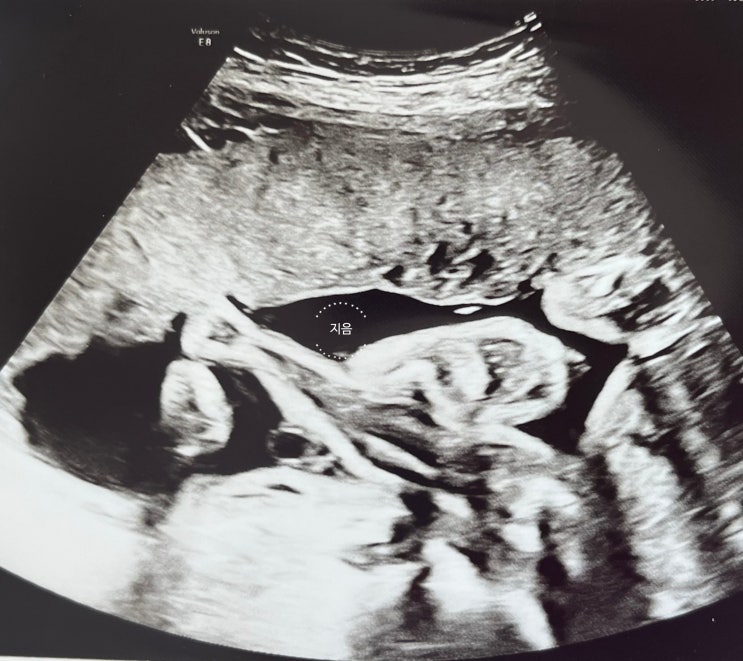

[임신일기] 27주 입체초음파와 베이비페이스

임신 10주 분당서울대병원 전원 임신 12주 임당 검사 (119 통과) NT초음파 (콧대, 목덜미 투명대 1.34mm ...